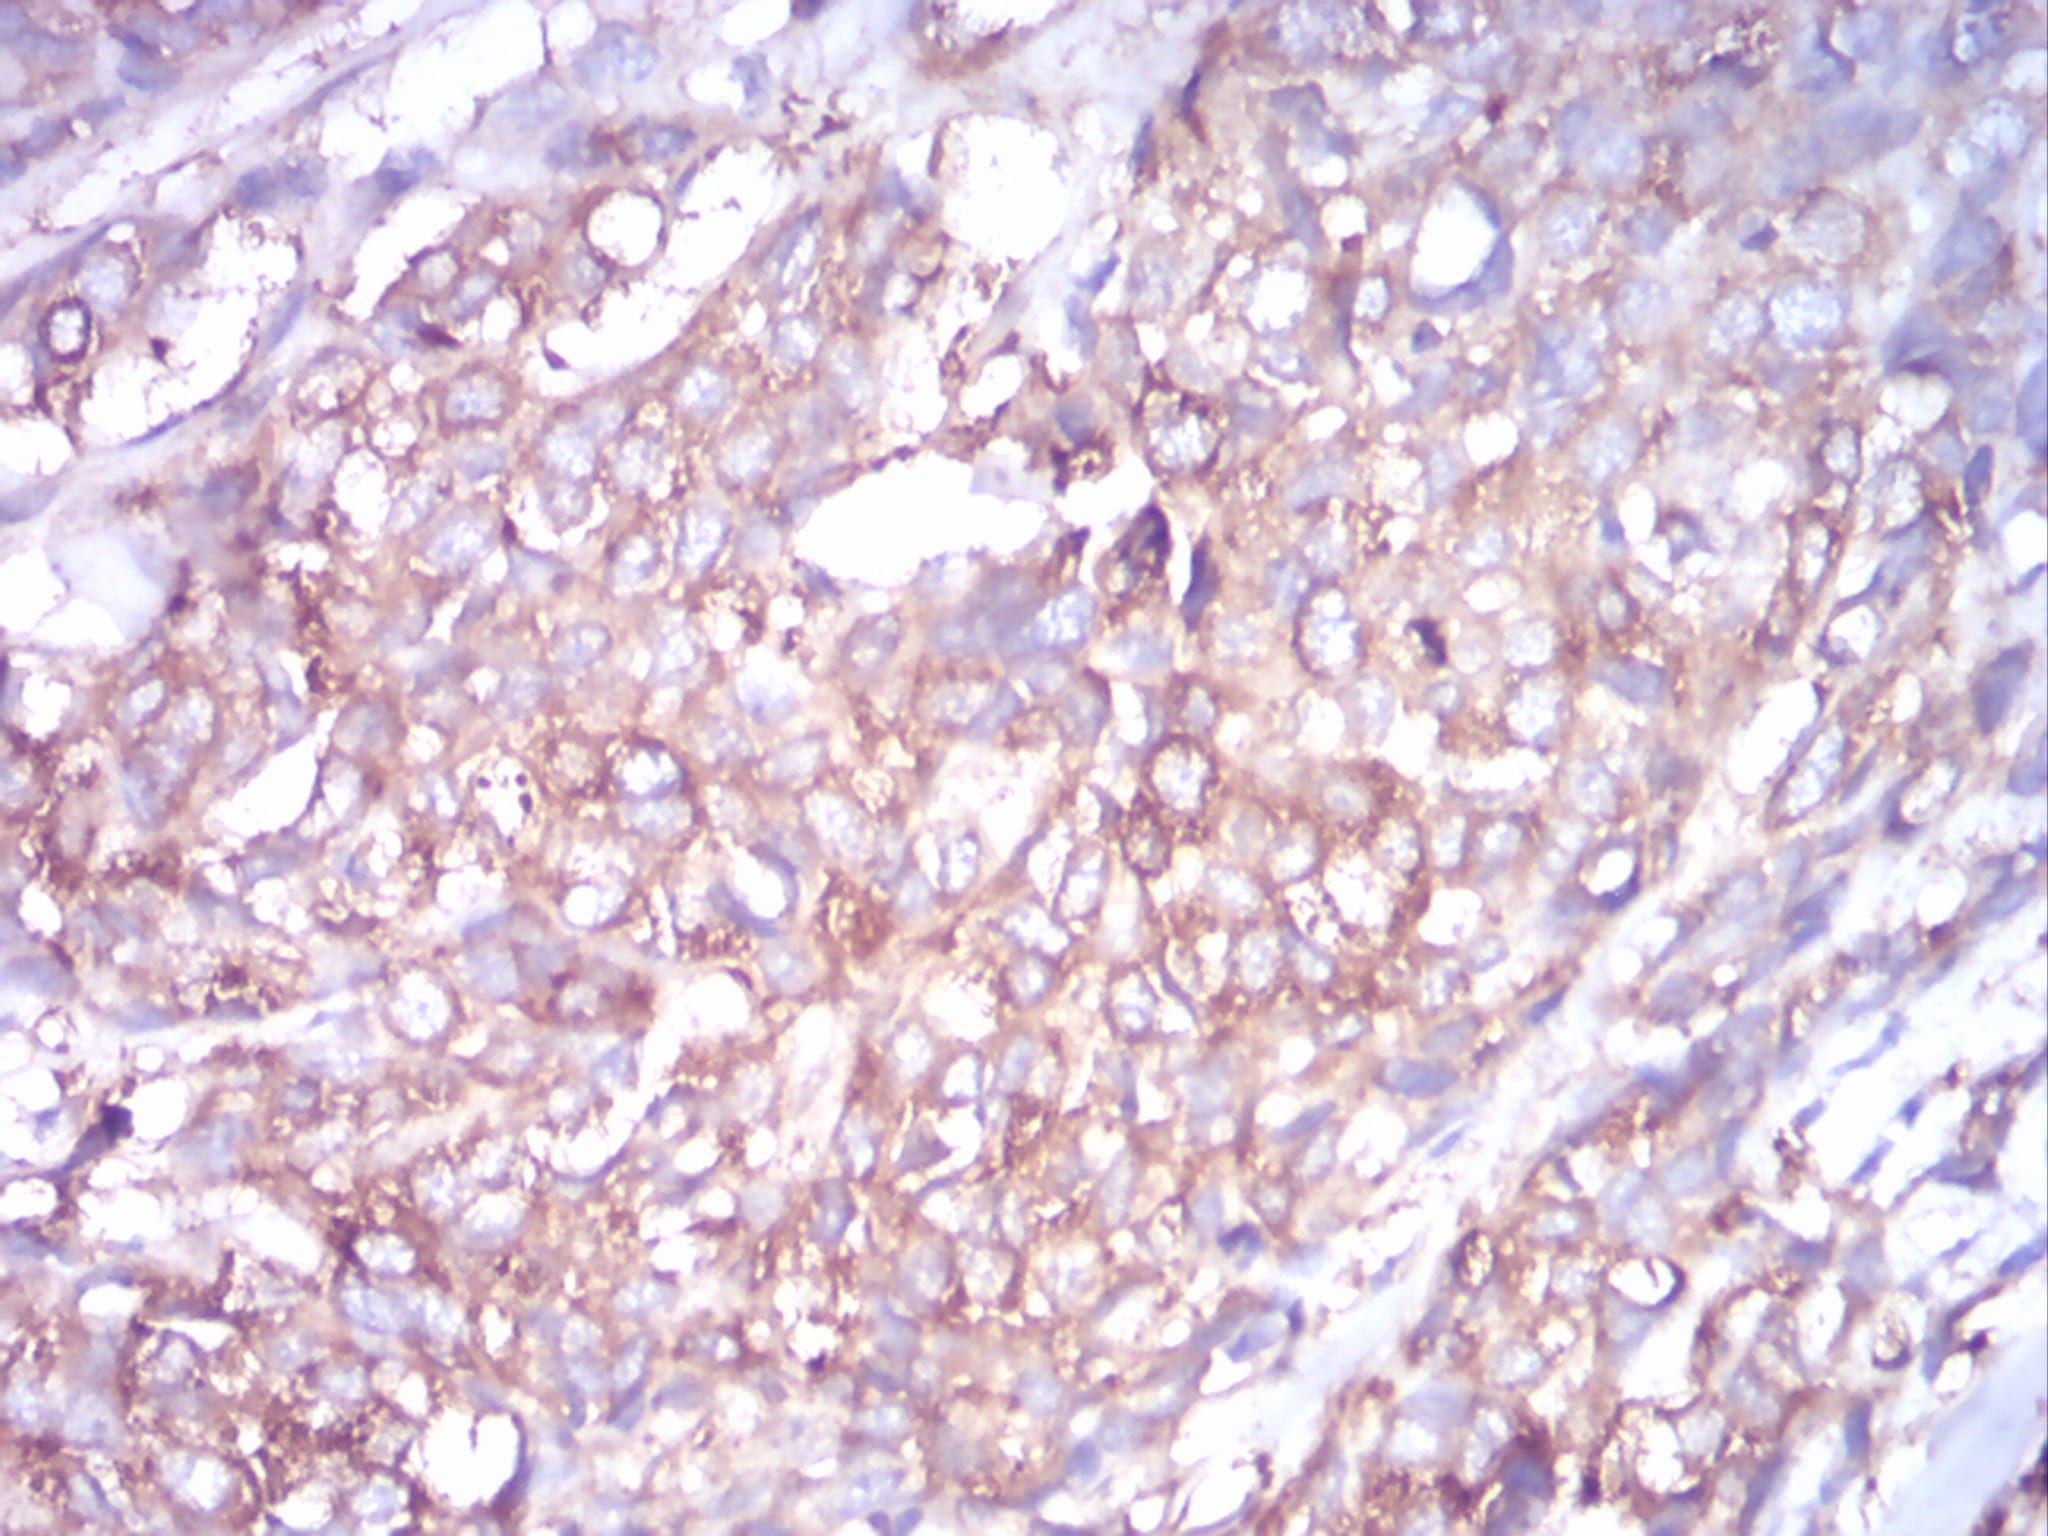

Immunohistochemical analysis of paraffin-embedded human ovarian cancer tissues using TUBB1 mouse mAb with DAB staining.

鄂公网安备42018502007531号